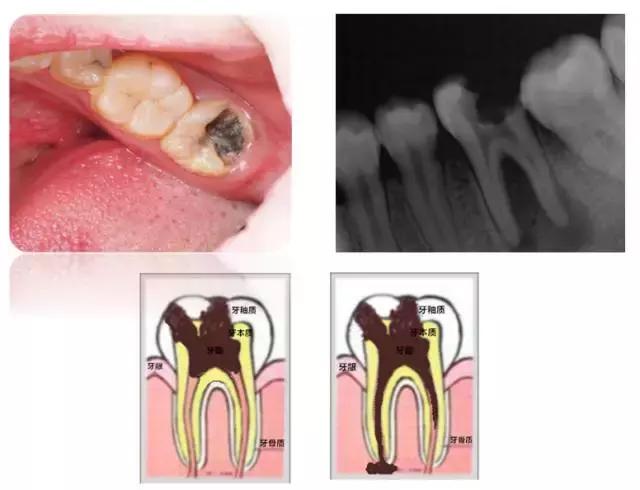

龋齿的形成是一个相对较缓慢的过程。根据龋齿的深度,我们分为三个不同的阶段,浅龋、中龋和深龋。不同的阶段有不同的症状。

当牙釉质持续的破坏腐蚀后,就会慢慢形成浅表的破坏。浅龋可能是黑色的窝沟或者很小的龋洞,也可以仅仅表现为白色的斑块。这个时候因为牙齿破坏小并且没有明显的症状往往很难引起人们的注意。然后龋洞逐渐扩大,进入到牙本质形成较大的龋洞,这时食物会卡在洞里面,有可能吃点甜食就会酸痛。再往下发展达到牙本质深层形成深龋时,症状就更明显了,冷热刺激时都会感到疼痛。像图中这颗牙破坏的范围很广,整个牙齿表面都变黑了。

当龋坏累及牙髓

深龋再往下发展会变成什么呢?当龋坏累及到牙神经,就会引发牙神经发炎和牙根发炎,我们称之为牙髓炎和根尖周炎。这时候疼痛会更剧烈,情况就比较严重了,治疗手段也会变得更复杂。所以说“小洞不补,大洞吃苦”,一发现龋齿就要去医院检查。